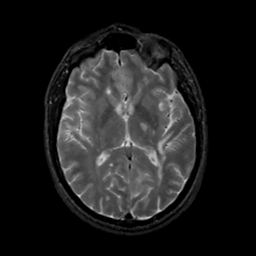

MR Study #12, May 12, 1991 -- Slice #26